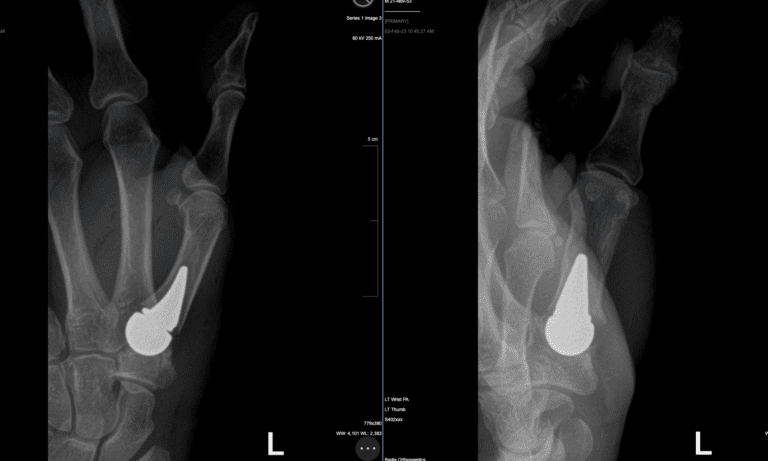

Biopro modular implant for base of the thumb arthritis – Impressive before and after xray!

Discover the innovative BioPro® Modular Thumb Implant, a groundbreaking solution for osteoarthritis of the thumb, offering effective pain relief while preserving thumb function and anatomy.

The BioPro® Modular Thumb Implant is a two-piece implant consisting of a head and a press-fit plasma-sprayed stem. The Modular Thumb is designed to address carpometacarpal (CMC) joint arthritis Warning: Viewer discretion is advised, content is intended for medical education.